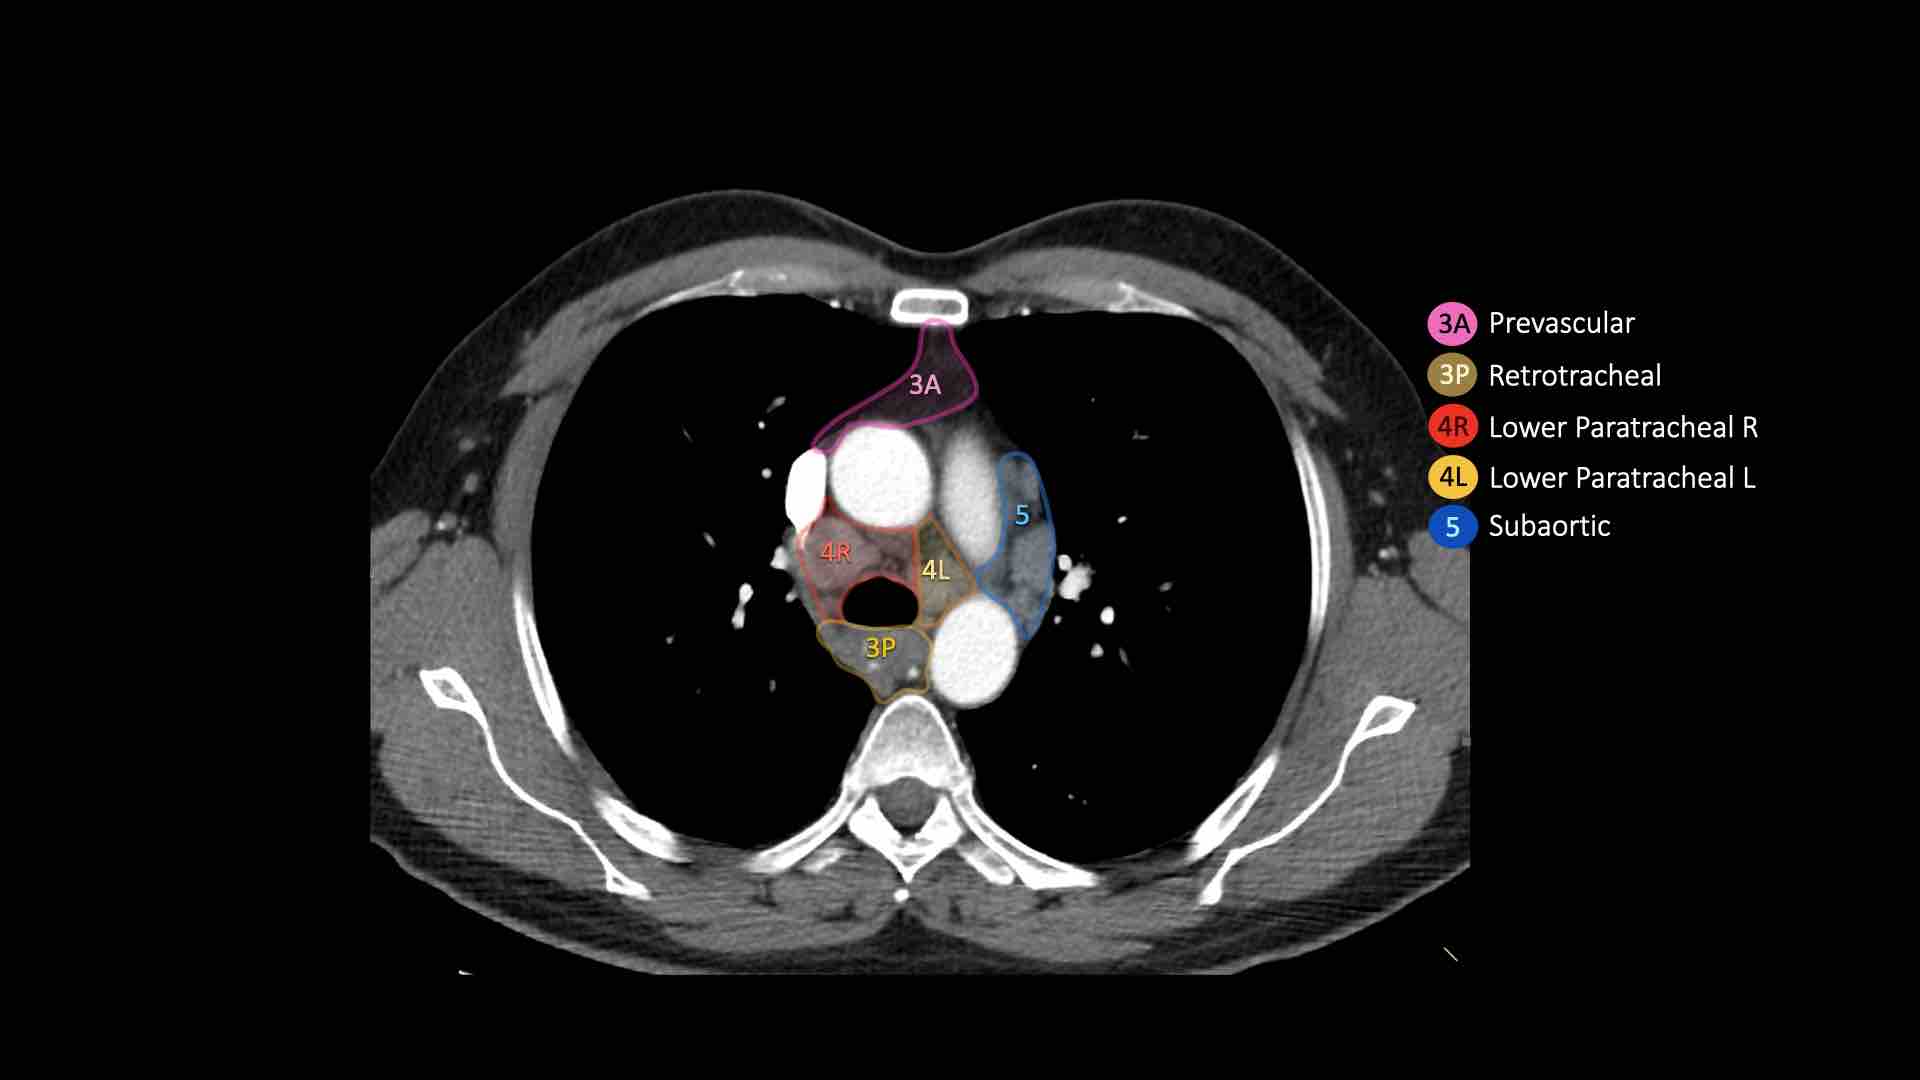

3A.Trước mạch máu

Các hạch này không tiếp giáp với khí quản như các hạch ở nhóm 2, mà nằm ở phía trước các mạch máu.

3P.Trước cột sống

Các hạch không tiếp giáp với khí quản như các hạch ở nhóm 2, mà nằm sau thực quản, tức là ở vị trí trước cột sống.

4R.Cạnh khí quản dưới

Từ điểm giao nhau giữa bờ dưới tĩnh mạch vô danh (tĩnh mạch tay đầu trái) với khí quản đến bờ dưới tĩnh mạch đơn.

Hạch nhóm 4R trải dài từ bờ bên phải đến bờ bên trái của khí quản.

4L.Cạnh khí quản dưới

Từ bờ trên của quai động mạch chủ đến bờ trên của động mạch phổi trái.

5. Dưới động mạch chủ

Các hạch này nằm trong cửa sổ phế động mạch (AP window), ở phía ngoài dây chằng động mạch.

Các hạch này không nằm giữa động mạch chủ và thân động mạch phổi mà nằm ở phía ngoài các mạch máu này.

4L. Hạch cạnh khí quản dưới bên trái

Hạch nhóm 4L là các hạch cạnh khí quản dưới nằm bên trái bờ trái của khí quản, giữa đường nằm ngang tiếp tuyến với bờ trên quai động mạch chủ và đường tiếp tuyến với bờ trên động mạch phổi trái.

Nhóm này bao gồm các hạch cạnh khí quản nằm ở phía trong dây chằng động mạch.

Hạch nhóm 5 (cửa sổ phế động mạch) nằm ở phía ngoài dây chằng động mạch.

Bên trái là hình ảnh ngay trên mức thân động mạch phổi, cho thấy các hạch cạnh khí quản dưới bên trái và bên phải.

Ngoài ra còn có các hạch nhóm 3 và nhóm 5.

Bên trái là hình ảnh ở mức phần dưới khí quản, ngay trên carina.

Bên trái khí quản là các hạch 4L.

Lưu ý rằng các hạch 4L này nằm giữa thân động mạch phổi và động mạch chủ, nhưng không nằm trong cửa sổ phế động mạch, vì chúng nằm ở phía trong dây chằng động mạch.

Hạch nằm bên ngoài thân động mạch phổi là hạch nhóm 5.